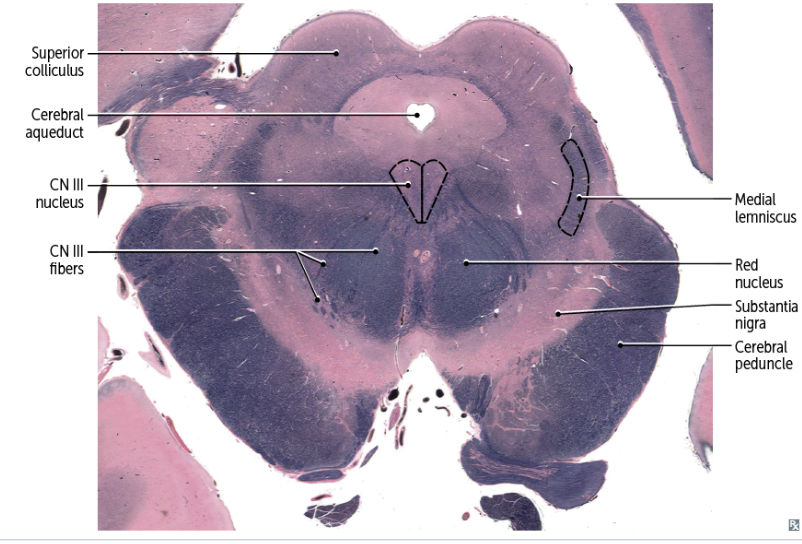

recognizable features of the MIDBRAIN in cross-section

A

-anterior/ventral: cerebral peduncles

-posterior/dorsal: superior or inferior colliculi

-cerebral aqueduct